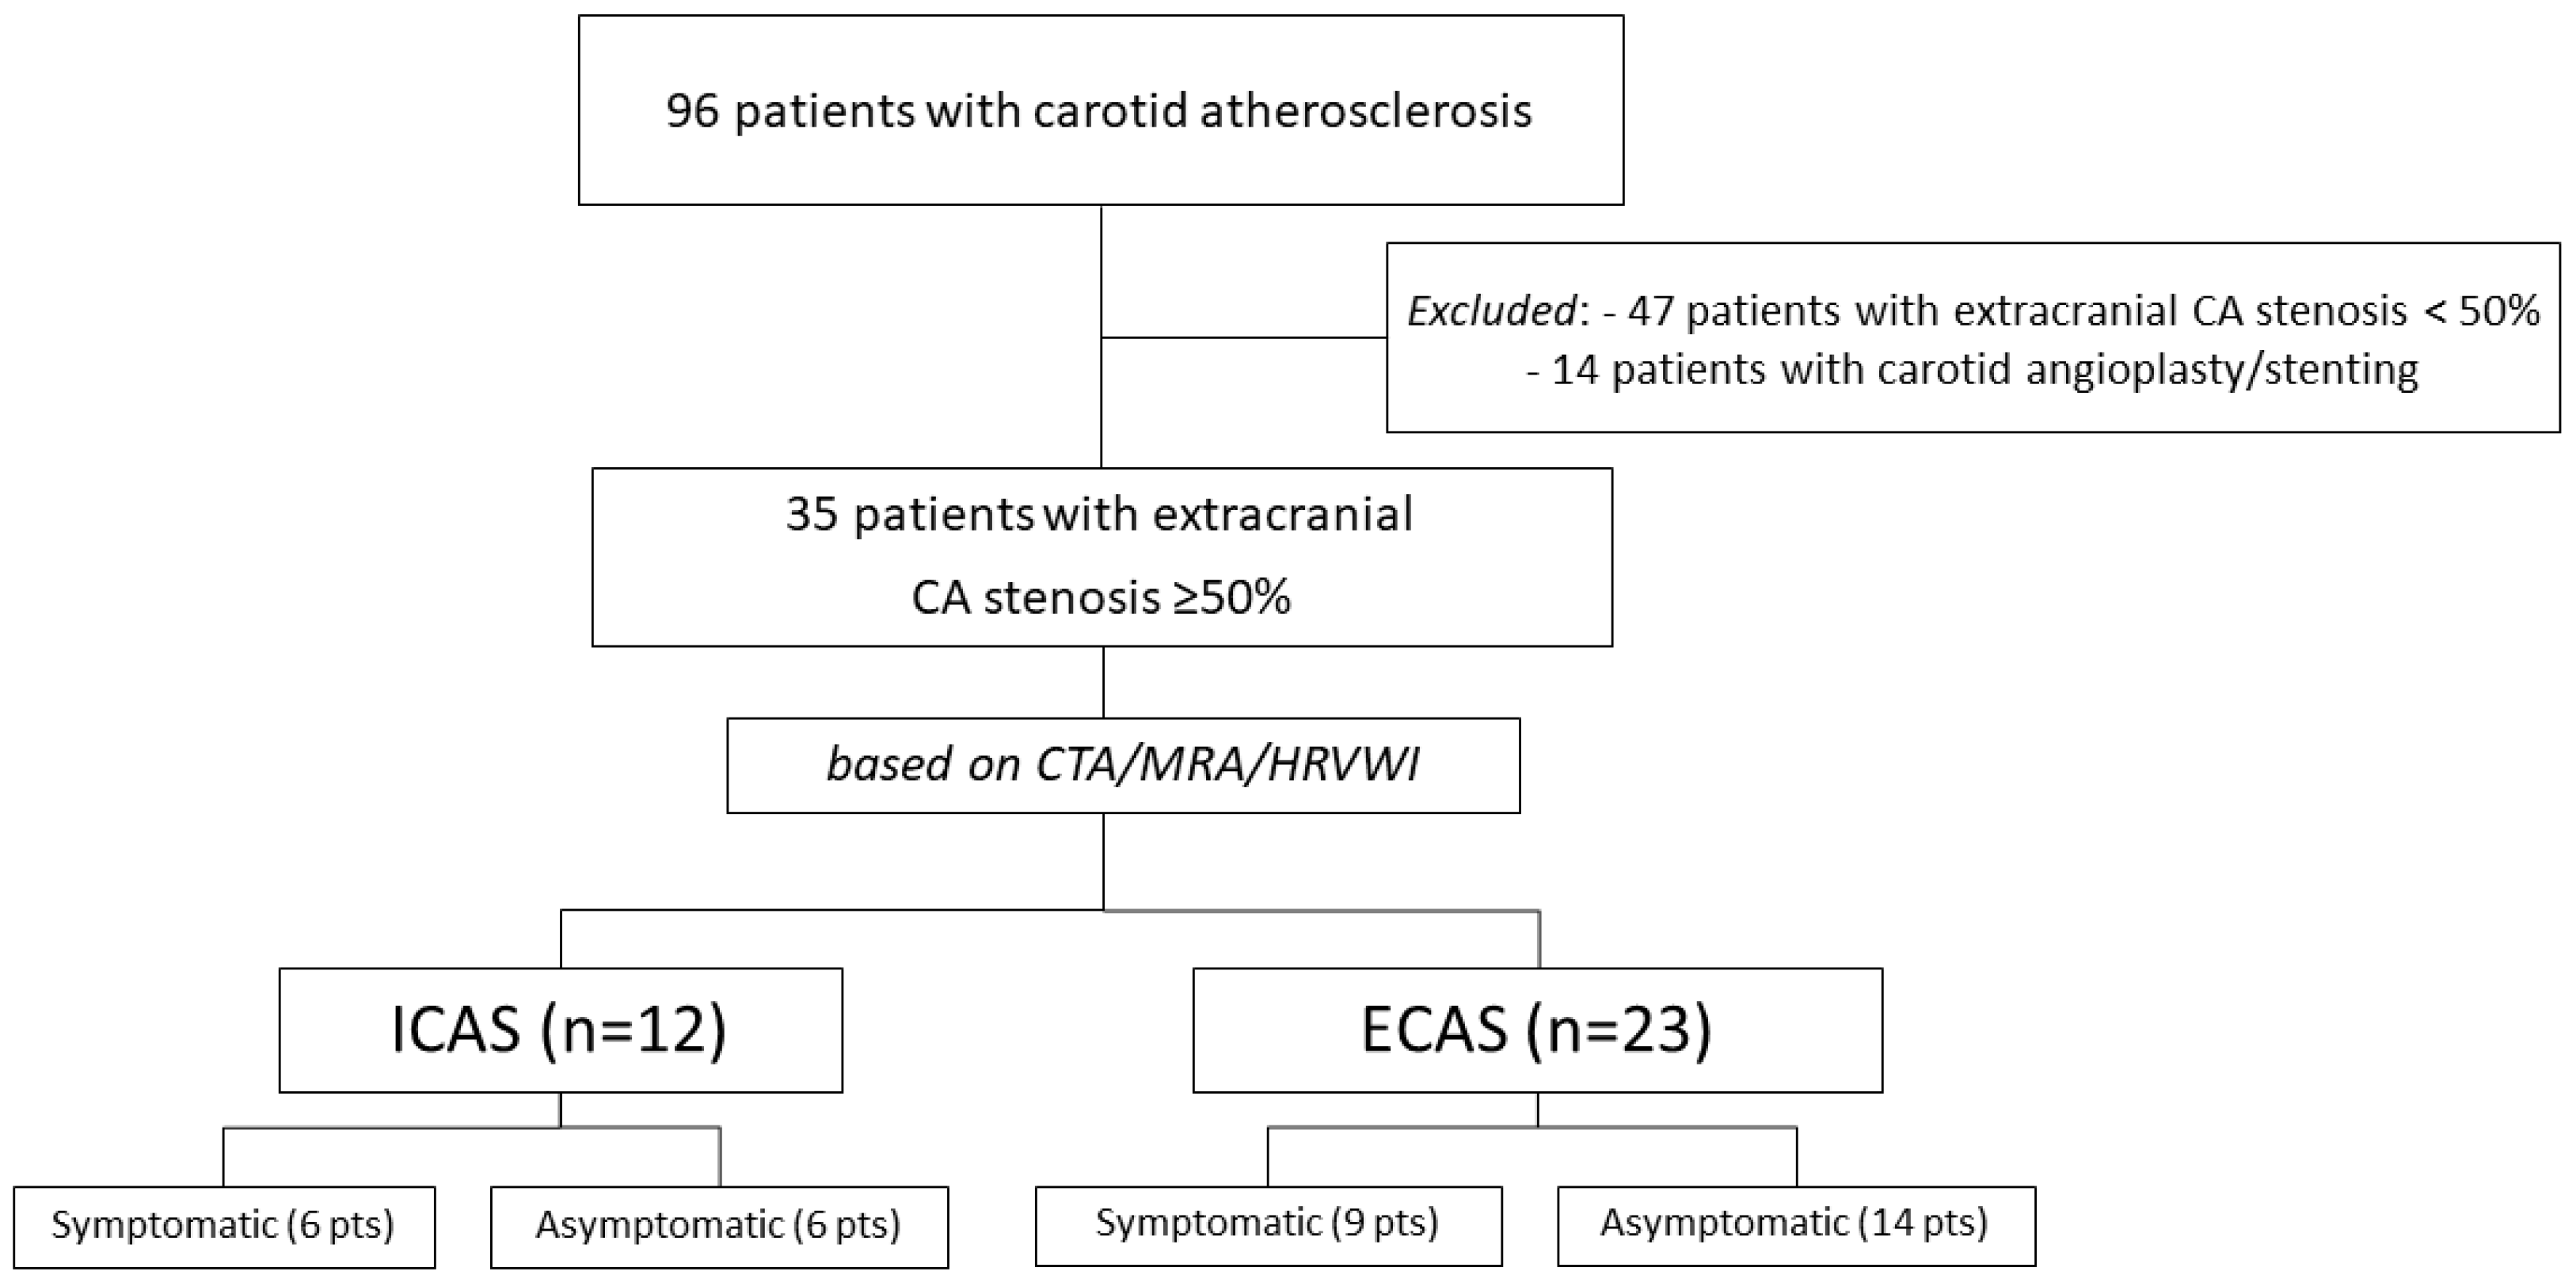

2.1. Study Population